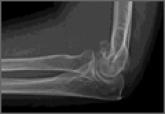

ArticleThe Role of Computed Tomography in Evaluating Intra-Articular Distal Humerus FracturesAuthor:Udofia AAPublish date: September 1, 2015 Computed tomography (CT) is often used to evaluate intra-articular distal humerus fracture patterns, but it increases radiation exposure and cost....Read More